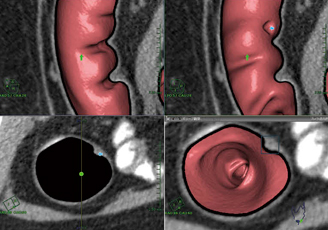

詳細読影では,仮想内視鏡画面の移動に合わせて,MPR像が常に中心位置で連動して表示されるため便利である。また,直交カット断面では,仮想内視鏡画面の移動に合わせて,オブリーク断面に直交し180°ずつ2つにカットして展開された断面が,仮想内視鏡竹割り画像として表示されるため,ハウストラ,大腸屈曲,ポリープの関係が直感的に理解しやすい。特に,脾彎曲部など屈曲が強い部位の観察がしやすい(図4)。比較表示では,仮想内視鏡画面とオブリーク断面,MPR像を同時に表示し,同期/非同期の切り替えもできるため位置合わせが行いやすい。このとき,仮想内視鏡画面における断面画像,クレンジング処理ON/OFF画像を選ぶことも可能である。

図4 脾彎曲部直交カット断面 脾彎曲部のように屈曲が強く観察が行いにくい場所でも,観察しやすい。

図4 脾彎曲部直交カット断面

脾彎曲部のように屈曲が強く観察が行いにくい場所でも,観察しやすい。